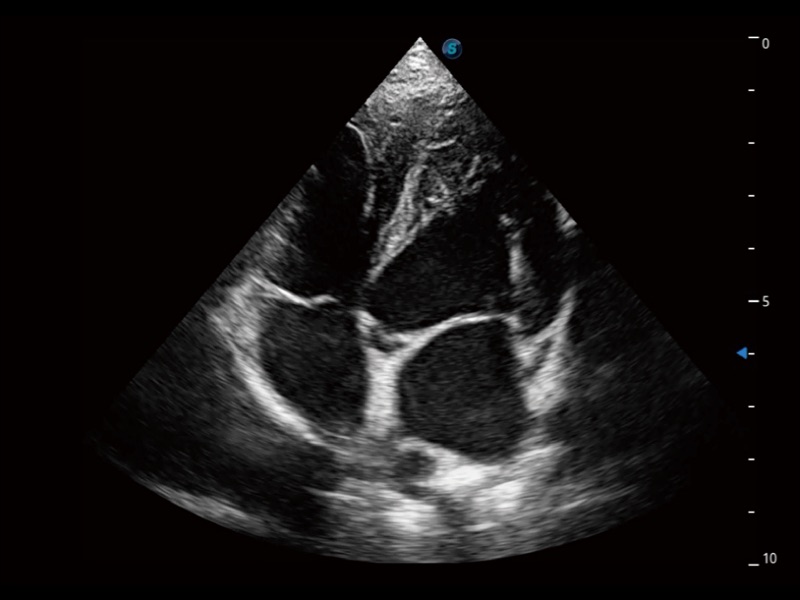

动物是人类最亲密的朋友和最值得信赖的伙伴。乐玩lewin国际也一直致力于探索动物专用的超声影像解决方案。全新推出的ProPet系列,是乐玩lewin国际在动物超声影像智能化、专业化、精准化的一次跨越式革新。动物不能用言语来表述自己的不适,通过超声影像,ProPet系列搭建了动物医生与不同物种沟通的“桥梁”,为动物医生注入了“治愈之力”。 ProPet 70将是您值得信赖的超声伙伴。它配备了复合材料线阵探头,帮助动物医生获得卓越精准的临床图像。同时ProPet 70直观便捷的操作体验以及专业的测量工具,可为不同体型和生理结构的动物带来全面临床评估,切实为动物医生提供智能、专业、精准的超声影像解决方案。

ProPet 70 进一步提升了微米成像算法,更加注重对基础原始图像的还原和保留,在有效减少斑点噪声、增强组织边界显示的同时,避免过度优化丟失真实的解剖信息。

ProPet 70专为动物医生设计,对不同的动物体型和生理结构作出了针对性的优化。通过动物影像专用软件,可满足个性化的应用需求,帮助动物医生获得更精确的诊断数据。

ProPet 70 全新的动物超声智能软件和丰富的探头群,为动物医生提供了高清晰度和精细分辨率的图像,无论在宠物、马科、畜牧还是实验室动物等应用中都可以轻松应对,为您的日常工作带来满意的体验。